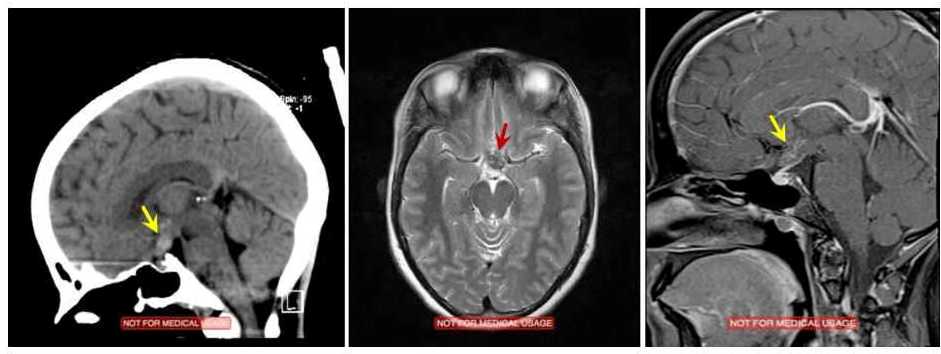

Fig. 3 Hypothalamus cavernoma Popcorn appearance yellow and red arrows .

Keeping in view visual field defects and optic atrophy and MRI MRV and MRA was done and she was diagnosed to have Hypothalamic cavernoma .